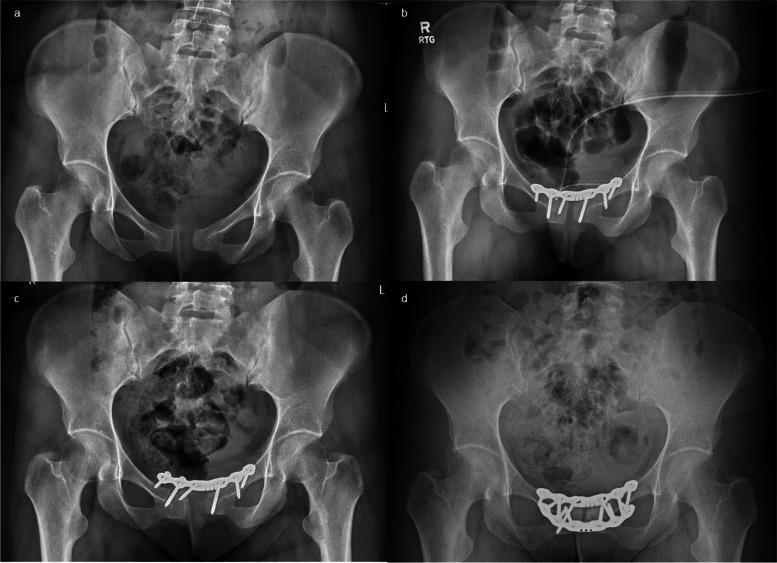

Five women, ranging in age from 25 to 38, who experienced peripartum symphysis rupture were primarily treated with a conservative approach. Patients who did not show improvement and met certain criteria, such as experiencing pain starting from childbirth, having a separation in the pubic bone of more than 10 mm, and/or having a vertical instability greater than 5 mm, were recommended to undergo surgery. The average length of time between childbirth and surgery was 5.6 months, ranging from 1 to 14 months. One patient was treated with an external fixator, another patient received a combination of an external fixator and an anterior plate, and three patients were treated with anterior plates. In four cases, we observed a failure in fixation and a partial or complete loss of reduction. The plate and screws were removed in one case, and in three cases, revision surgery was performed. One case involved using a larger plate, while the other used 90-90 plating, known as "box plate fixation." The mean follow-up was 7.4 years. Two cases had good results, and two had excellent results on the Lindahl scale.

5名年龄在25至38岁之间的围产期耻骨联合破裂女性最初采用保守治疗。未显示改善且符合某些标准的患者,如自分娩起就经历疼痛、耻骨分离超过10毫米和/或垂直不稳定大于5毫米,被建议接受手术。分娩至手术的平均时间为5.6个月,范围为1至14个月。1例患者采用外固定架治疗,另1例患者接受外固定架和前路钢板联合治疗,3例患者采用前路钢板治疗。4例中,我们观察到固定失败以及部分或完全复位丢失。1例取出了钢板和螺钉,3例进行了翻修手术。1例使用了更大的钢板,另1例使用了90-90钢板固定,即“盒式钢板固定”。平均随访7.4年。根据林达尔量表,2例效果良好,2例效果极佳。